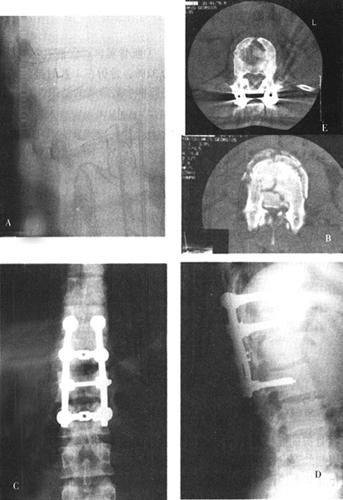

图13-40 25岁男性,被搅拌机搅伤,术前X光片和CT(A、B、C)可见L1骨折脱位,层叠于T12上手术采用右侧前方入路。L1椎体切除后获得复位,大块髂骨植骨和Z-plate Ⅱ内固定

图13-41 28岁女性,T11爆裂骨折,术前侧位片(B)见骨折碎片向后压迫脊髓。前路手术减压,Z-plate Ⅱ固定,使用了钛网。因系统放置在椎体右侧,所以板的头部向下